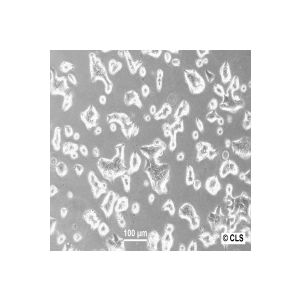

Breast cancer cell lines